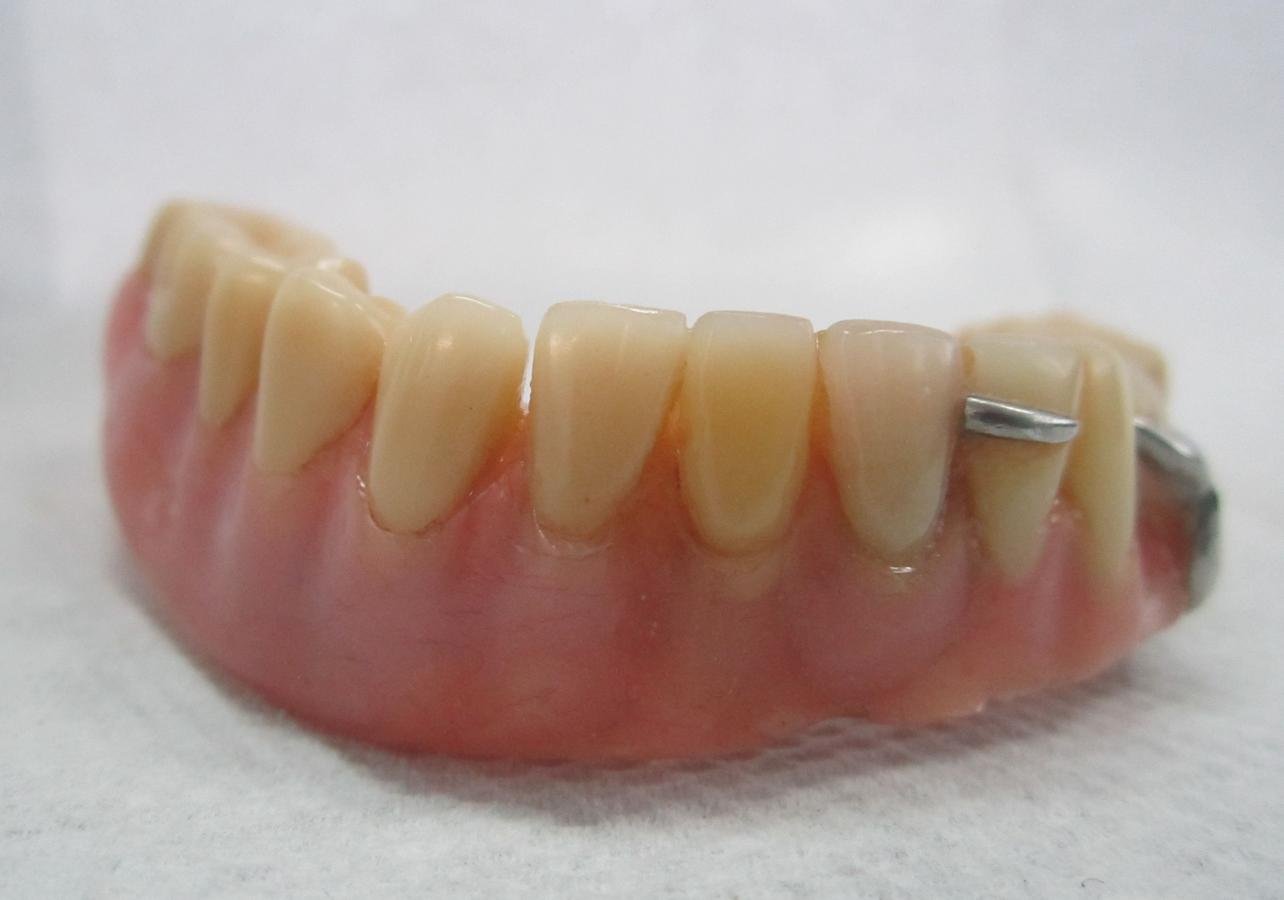

TRATAMIENTO FINAL

Prótesis total superior e inferior elaboradas con Eclipse